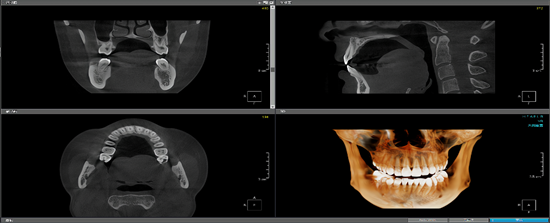

工作室团队成员目前包括李思博士、何远清老师、胡晨恺医生(南昌大学第二附属医院心内科主治医师)。另现有7名学生成员,包括20级1名、21级1名、22级5名,学生成员目前的研究主题包括:基于深度学习的冠脉造影狭窄智能检测技术研究(如图1所示);基于神经网络的智慧城市停车位检测技术研究(如图2所示);基于深度学习的口腔CT牙槽骨分割技术研究等(如图3所示)。

图3:基于深度学习的口腔CT牙槽骨分割技术研究